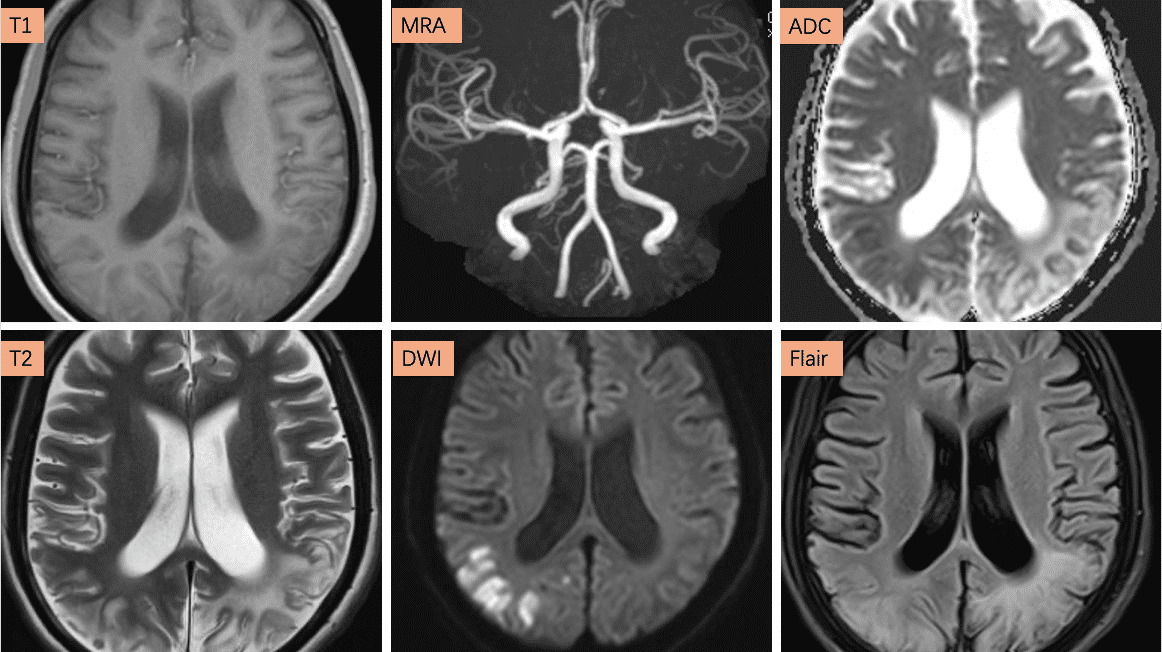

图2,为完整血管病MR检查序列(包含T1、T2、Flair、DWI、ADC及MRA),提示颅内多发片状长T1长T2信号影,局部皮质见线条状稍短T1信号,双侧颞顶枕叶为著,局部双侧侧脑室旁见对称性斑片状稍长T1长T2信号灶,边界模糊。